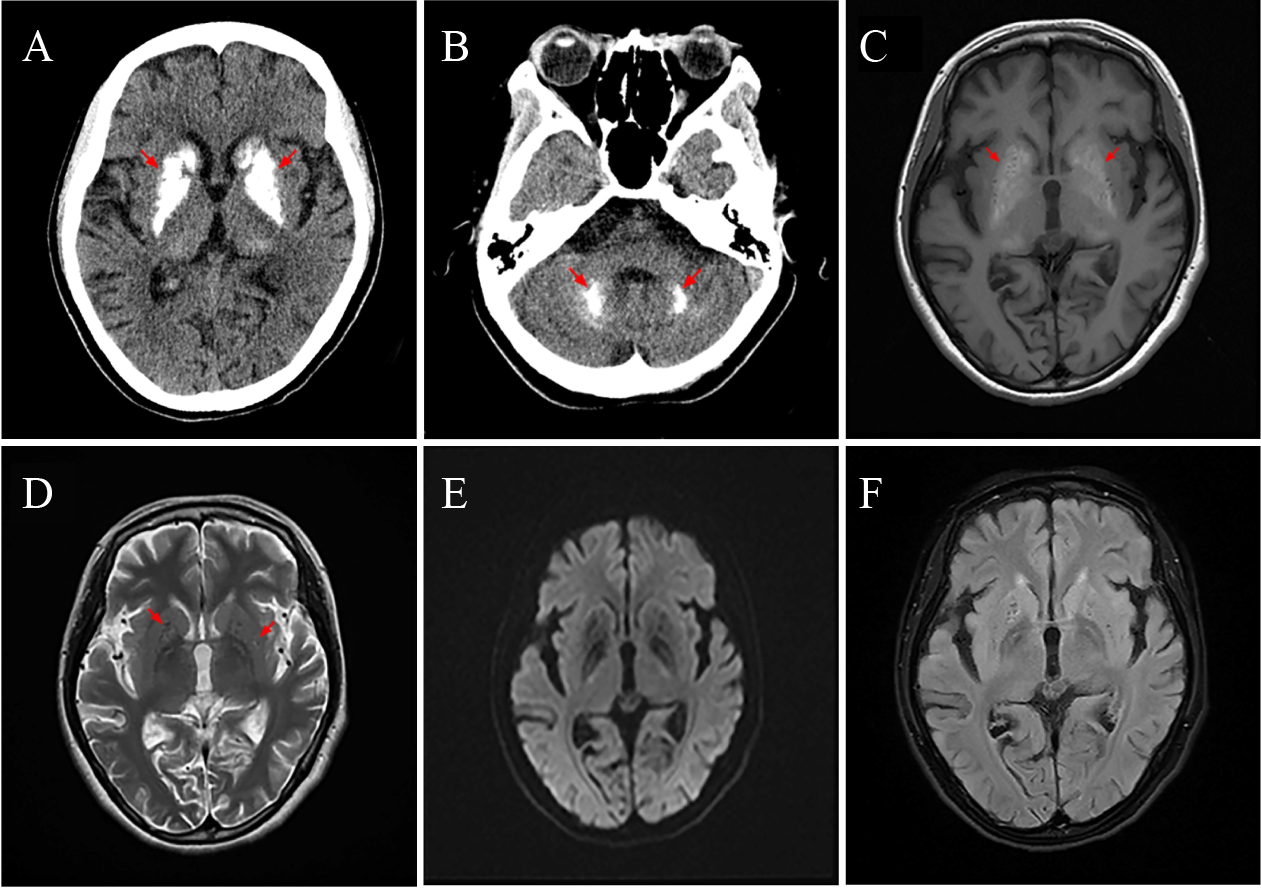

In the emergency department, the patient’s convulsive state was alleviated through intravenous infusion of valproate. She was in a fragile condition with a temperature of 37.7 °C, heart rate of 111 bpm, and blood pressure of 105/69 mmHg. No abnormal signs were detected on the neurological examination. Blood tests showed elevated C-reactive protein level (52.8 mg/L, reference interval: 0–6 mg/L), leukocyte count (24.91 × 109/L, reference interval: 3.5 × 109/L–9.5 × 109/L), neutrophil count (22.22 × 109/L, reference interval: 1.8 × 109/L–6.3 × 109/L), lactate level (2.56 mmol/L, reference interval: 0.5–2.2 mmol/L), and creatinine kinase level (256 IU/L, reference interval: 40–200 IU/L). Liver function, kidney function, thyroid function, and parathyroid hormone levels were within the normal range. Chest computed tomography (CT) revealed bilateral pulmonary infections. Brain CT demonstrated calcifications involving the bilateral basal ganglia, thalamus, and dentate nuclei of cerebellum (Fig. 1A and 1B), with subsequent magnetic resonance imaging (MRI) corroborating these findings (Fig. 1C–1F). The electroencephalography demonstrated occasional spike-and-wave discharges predominantly over the bifrontal and anterior-midtemporal areas (Fig. S1). Exome sequencing did not detect any pathogenic variants, while mitochondrial DNA analysis by long PCR revealed the m.3243A>G mutation with a heteroplasmy level of 32% in blood. The mutation was confirmed by Sanger sequencing (Fig. 2). Due to the decline in blood heteroplasmy levels with advancing age [7], we further calculated an age-adjusted heteroplasmy level of 72%. Mitochondrial DNA in other tissues was not analyzed due to lack of consent. We diagnosed the patient with MERRF and initiated levetiracetam for seizure control. Coenzyme Q10 and L-arginine were administered to mitigate oxidative stress and improve mitochondrial metabolism. The patient was discharged for outpatient follow-up after symptom resolution.